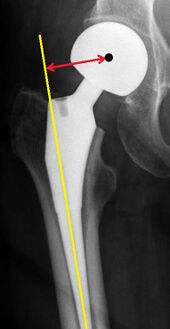

Leg length discrepancy after hip replacement is calculated as the vertical distance between the middle of the minor trochanters, using the acetabular tear drops[78] or the transischial line[7] as references for the horizontal plane. A discrepancy of up to 1 cm is generally tolerated.[78][7]

Center of rotation: The horizontal center of rotation is calculated as the distance between the acetabular teardrop and the center of the head (or caput) of the prosthesis and/or the native femoral head on the contralateral side.[78] The vertical center of rotation instead uses the transischial line for reference.[78] The parameter should be equal on both sides.[78]